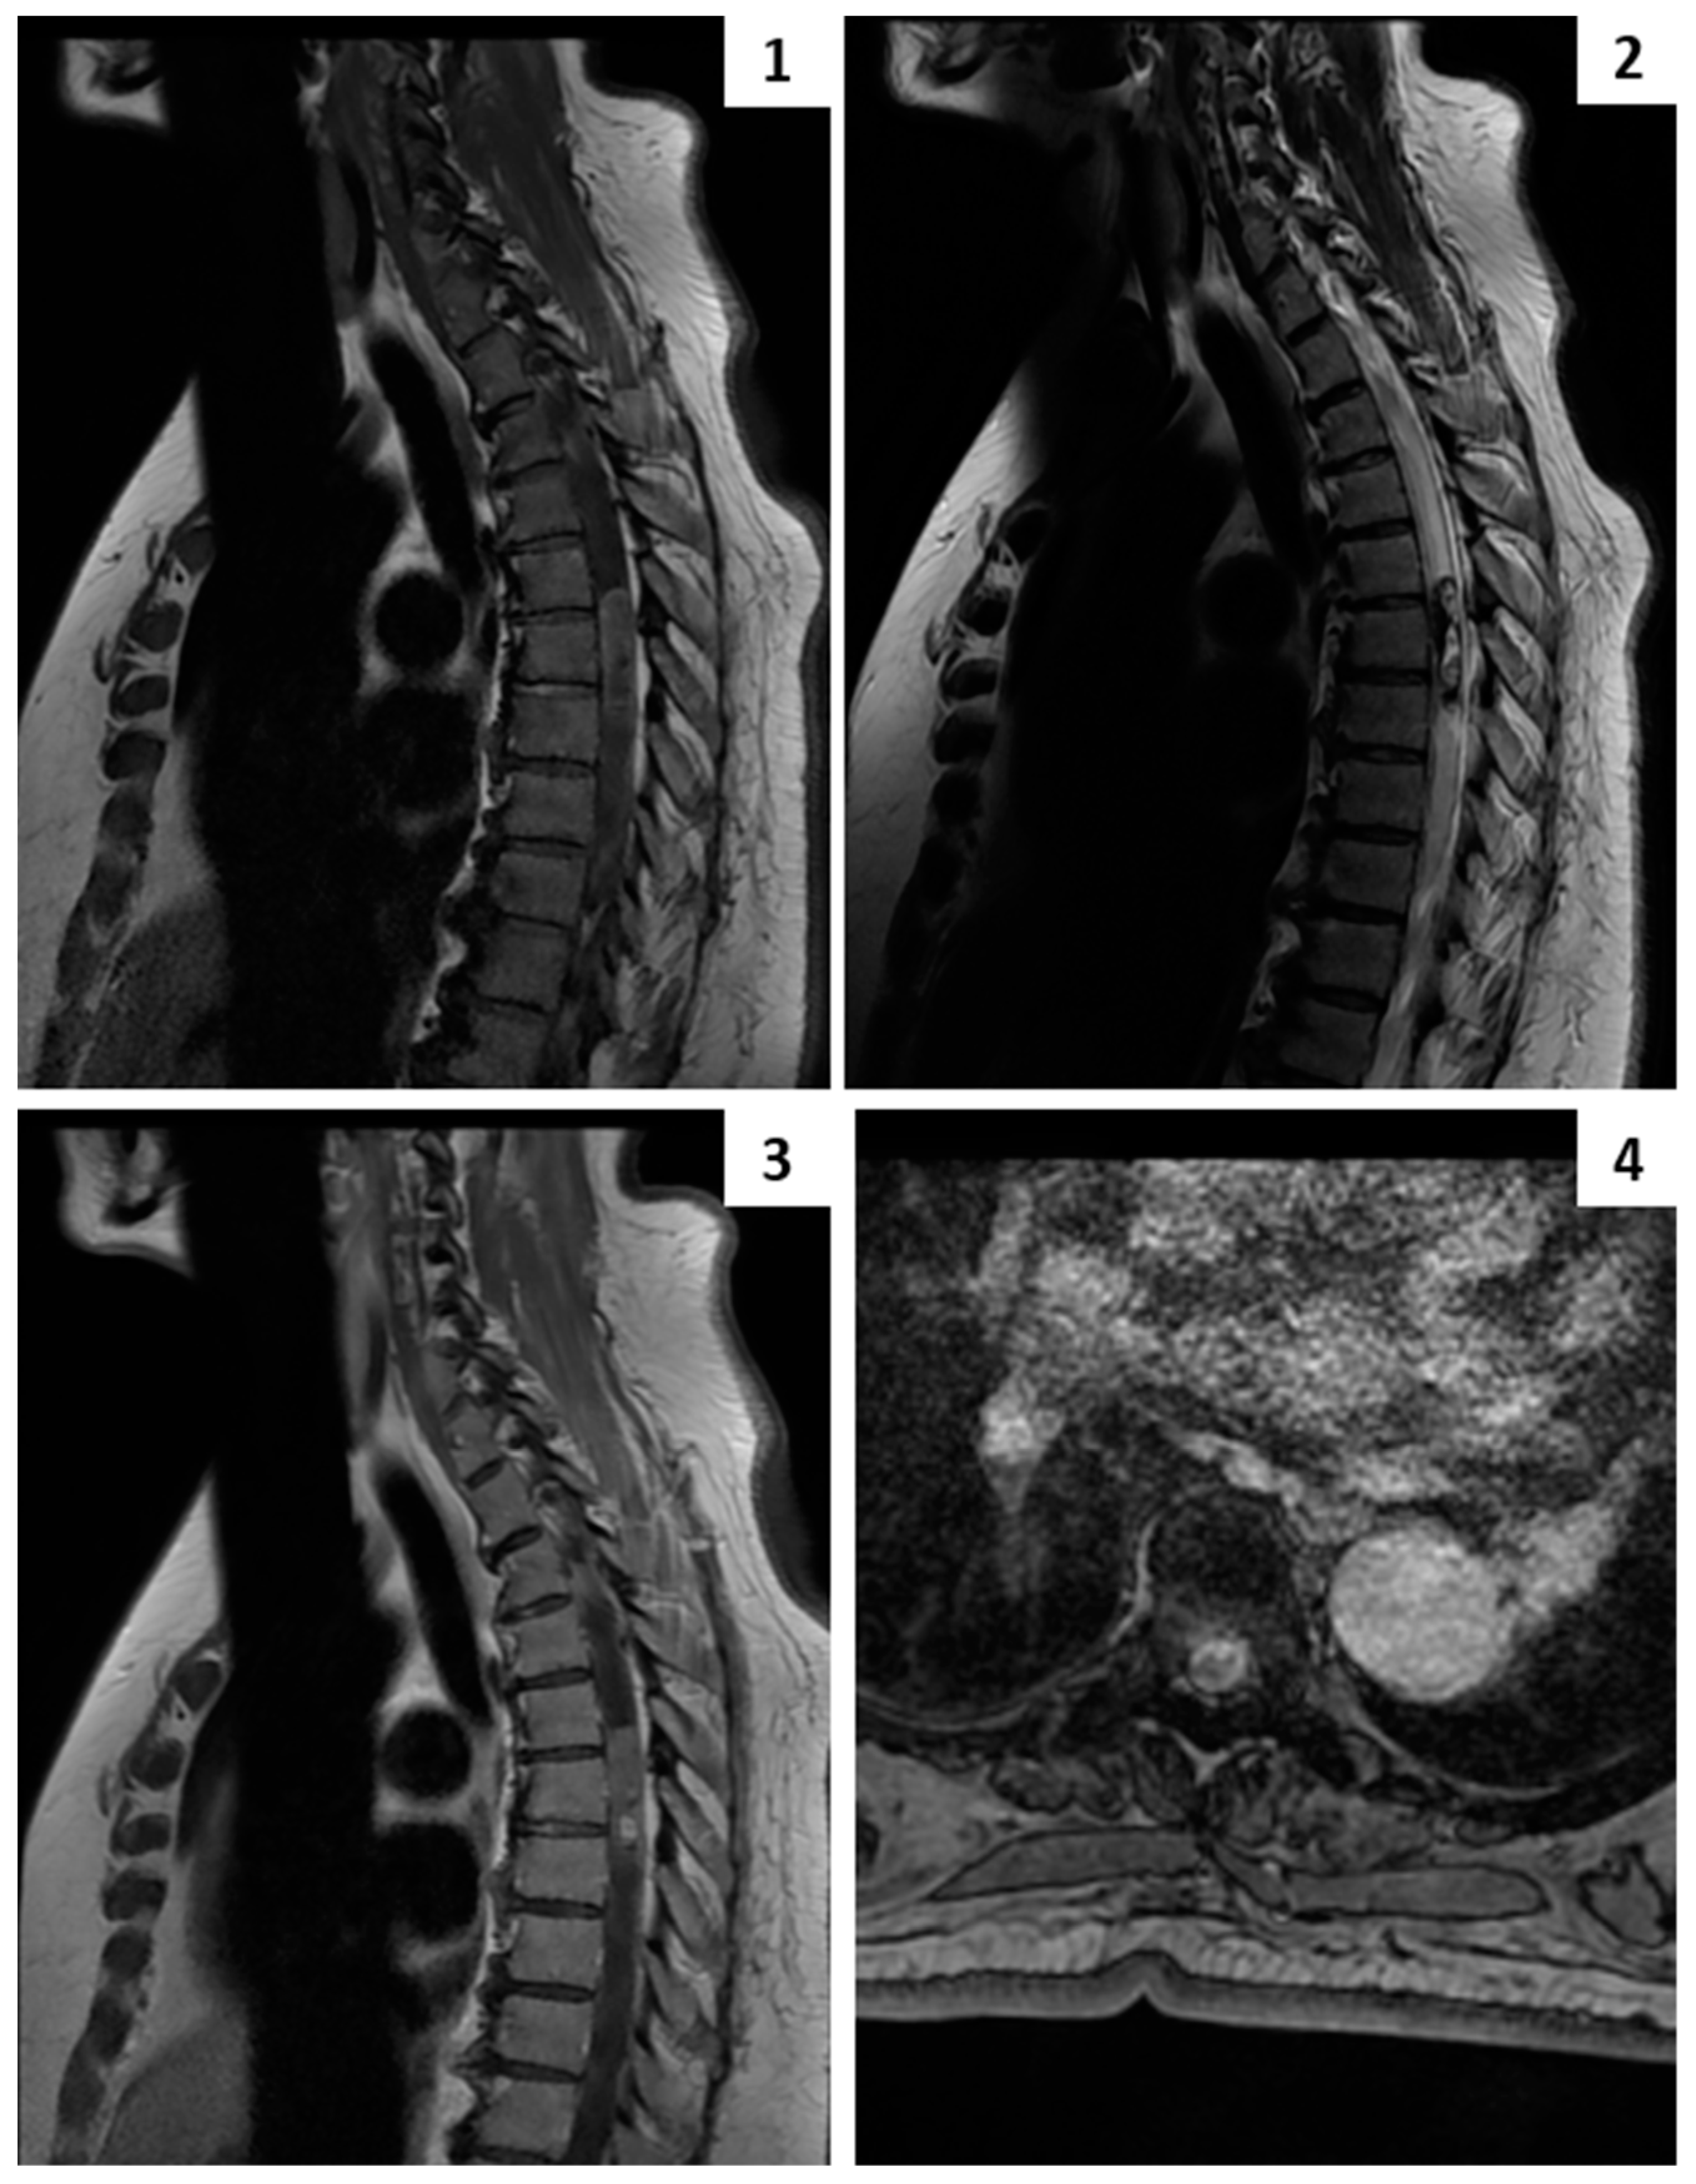

4.2. Imaging Examination